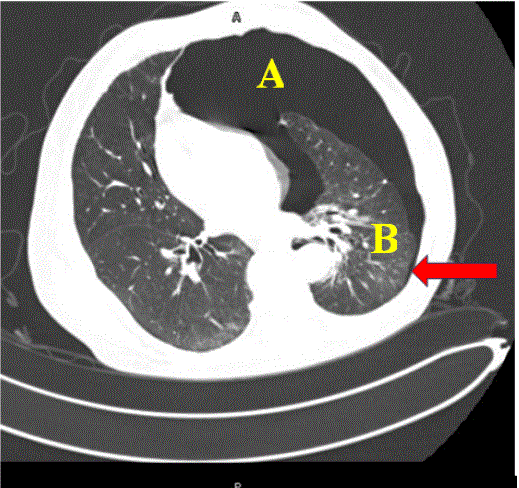

In the clinical case presented, the complete pneumothorax corresponds as defined by Kyoung MR, et al [12]. and will also lead to lung collapse causing total atelectasis. Let us remember that this atelectasis pathophysiologically occurs due to the absence of peripheral expansion of the lung and will be expressed in the x-ray study once all the trapped gas that occurs in the alveolar exchange has been absorbed, which begins when this exchange mechanism is stopped [13]. Due to this, in the images obtained ultrasound in the case, the lung can be seen as a collapsed mass in which a static or absent bronchogram is observed. The visceral pleura will not be in contact with the visceral pleura or will be too far medial that pleural sliding cannot be detected in the ultrasound image. It should not be strange, as in this case, in patients with total collapse of the lung, that the identification of this point called by the authors as “atelectatic point” could be a support point equivalent to the “lung point”, which could not be visualized, once identifying in the anterior zones the signs that reflect the loss of contact between the visceral and parietal pleura, and identifying in the region of the posterior axillary line the atelectatic lung, which is located in the anterolateral and inferior quadrants of the thorax [14], with the dynamic respiratory changes that make the image of a collapsed lung appear upon contact with the thoracic wall during expiration (Image A) and disappear with inspiration generating the typical image that is seen in pneumothorax (Image B). This finding is undoubtedly repeat over and over again with ventilatory dynamics, allowing us to assess its reproducibility in the case of complete pneumothorax, where an atelectatic lung will always coexist. This is a sign that we believe may have diagnostic value for complete pneumothorax. The images obtained were correlated with the simple CT scan performed on the patient as part of his comprehensive workup protocol (Image C).

Image C: Simple tomography of the patient's chest where the pneumothorax area can be seen (A), the atelectatic area (B) and the area of the posterior axillary line where the dynamic changes with inspiration - expiration can be observed (arrow) that document the "atelectatic point" described in the text.